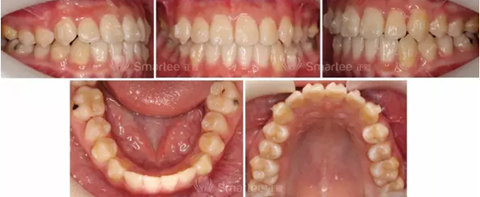

(口內(nèi)照片)

1)安氏Ⅲ類錯牙合

2)左側(cè)前牙反牙合

3)前牙區(qū)擁擠,個別牙扭轉(zhuǎn)

4)上頜中線右偏